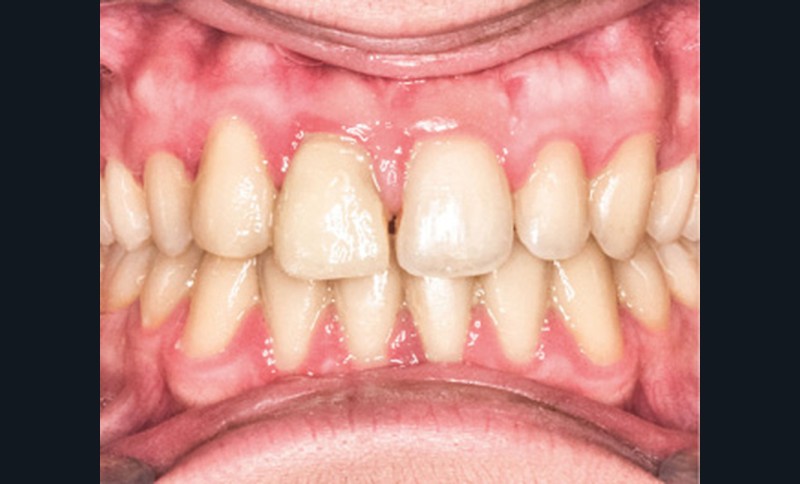

D’un point de vue occlusal, le patient, en denture adulte jeune stable, présente une classe II d’Angle bilatérale de 4 mm, associée à un encombrement maxillaire de 5 mm et mandibulaire de 2 mm. La face mésiale de 21 est centrée avec le plan sagittal médian, la non-concordance des médianes incisives est d’origine mandibulaire (déviation de la médiane mandibulaire vers la gauche) (fig. 1b-d).

Son incisive centrale supérieure droite (11) présente un défaut de structure amélaire sévère, compromettant une technique restaurative pérenne a minima. L’examen de la panoramique (fig. 1e) et de la radiographie rétroalvéolaire de 11 (fig. 1f) objective une fracture coronaire verticale, ainsi qu’une racine grêle et courbe, peut-être en rapport avec un ancien traumatisme [1]. Le rapport couronne clinique/racine clinique est défavorable.